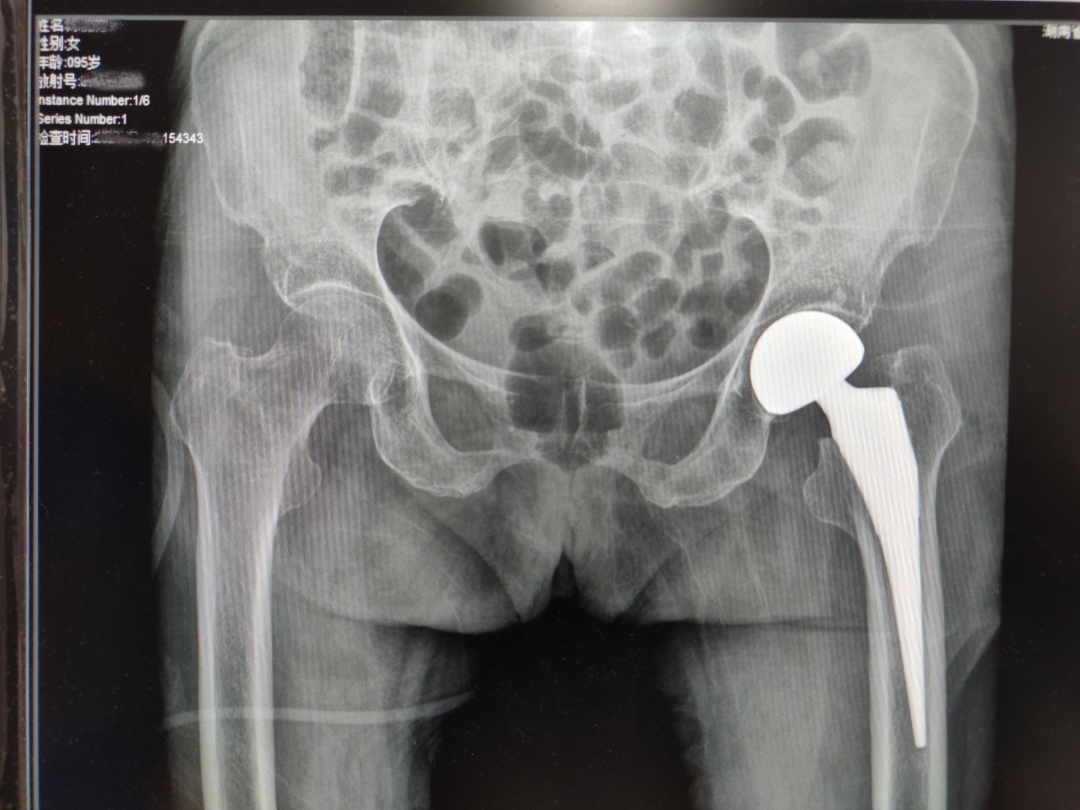

陈奶奶术后X光片

"三分治疗,七分护理",为了预防关节脱位、感染、压疮、坠积性肺炎、深静脉血栓等并发症,术后外二科医护人员积极指导陈奶奶进行踝泵运动、正确摆放体位,帮助翻身拍背,促进早期康复。在手术后第三天,陈奶奶就能借助助行器下床活动,一周后顺利出院。